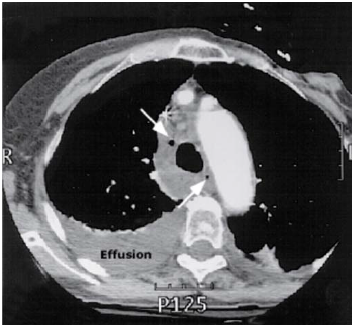

Disponível em: <www.uptodate.com>. Acesso em: 16 fev. 2023.

Um homem de 41 anos de idade apresentou dor torácica de início abrupto após libação alcoólica, seguida de vários episódios de vômitos. O estudo radiológico de tórax evidenciou derrame pleural à esquerda, sendo submetido a drenagem torácica com saída de líquido achocolatado e resíduos alimentares. Com base nessas informações, assinale a alternativa que designa a síndrome supracitada.